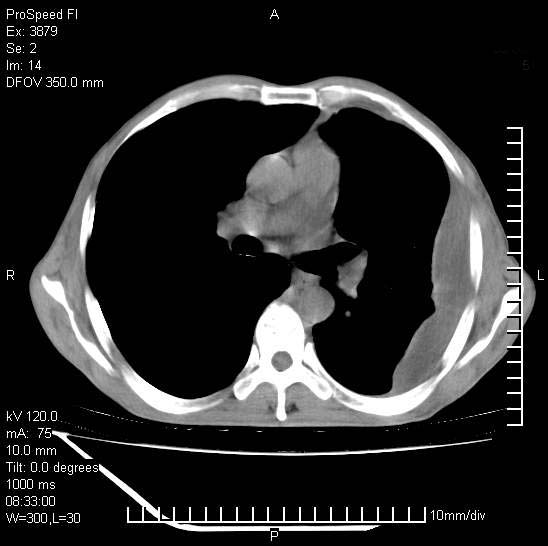

以下是引用37度在2008-6-6 11:20:00的发言:[br]1.包裹性积液,多考虑结核性;[br]2.穿刺术后改变。

以下是引用312nanyang在2008-6-6 15:12:00的发言:[br]基本支持楼主意见[br]疑问?左下肺支气管旁的软组织(16层)密度怎么解释?淋巴结还是斜裂胸膜增厚所致?能否增强进一步检查